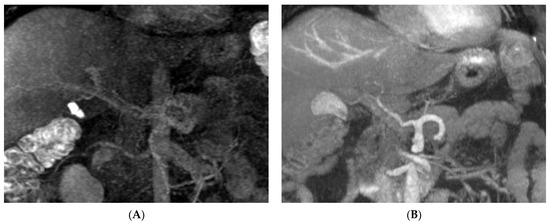

3. Results